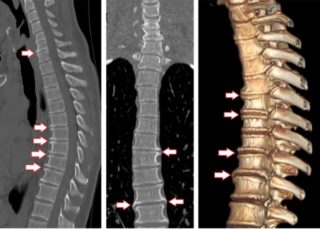

Чтобы определить, что именно могло защемить нервные окончания, и по каким причинам это произошло, нужно провести КТ или МРТ. Это позволит оценить состояние позвоночника и выявить повреждение или искривление межпозвонковых дисков. Электромиография помогает определить наличие повреждения нервных окончаний, отвечающих за двигательную активность определенных групп мышц.

Основные диагностические мероприятия, которые проводятся для выявления причины защемления нерва сзади со стороны лопатки – МРТ и КТ. По результатам рассматривают состояние позвоночного столба на уровне грудного отдела и в других сегментах. Таким способом можно обнаружить остеофиты, опухоли, кисты, другие новообразования.

- магнитно-резонансная или компьютерная томография – покажет наличие дефектов межпозвоночных дисков и патологических искривлений позвоночника и мышц;

- электромиография – определяет дефекты нервных окончаний, которые отвечают за функцию мышц. Процедура осуществляется путем введения в мышечную ткань электродной иглы;

- исследование нервных окончаний на проводимость с помощью тестов определения поврежденных нервов – к кожным покровам присоединяются электроды, по которым передаются слабые импульсы;